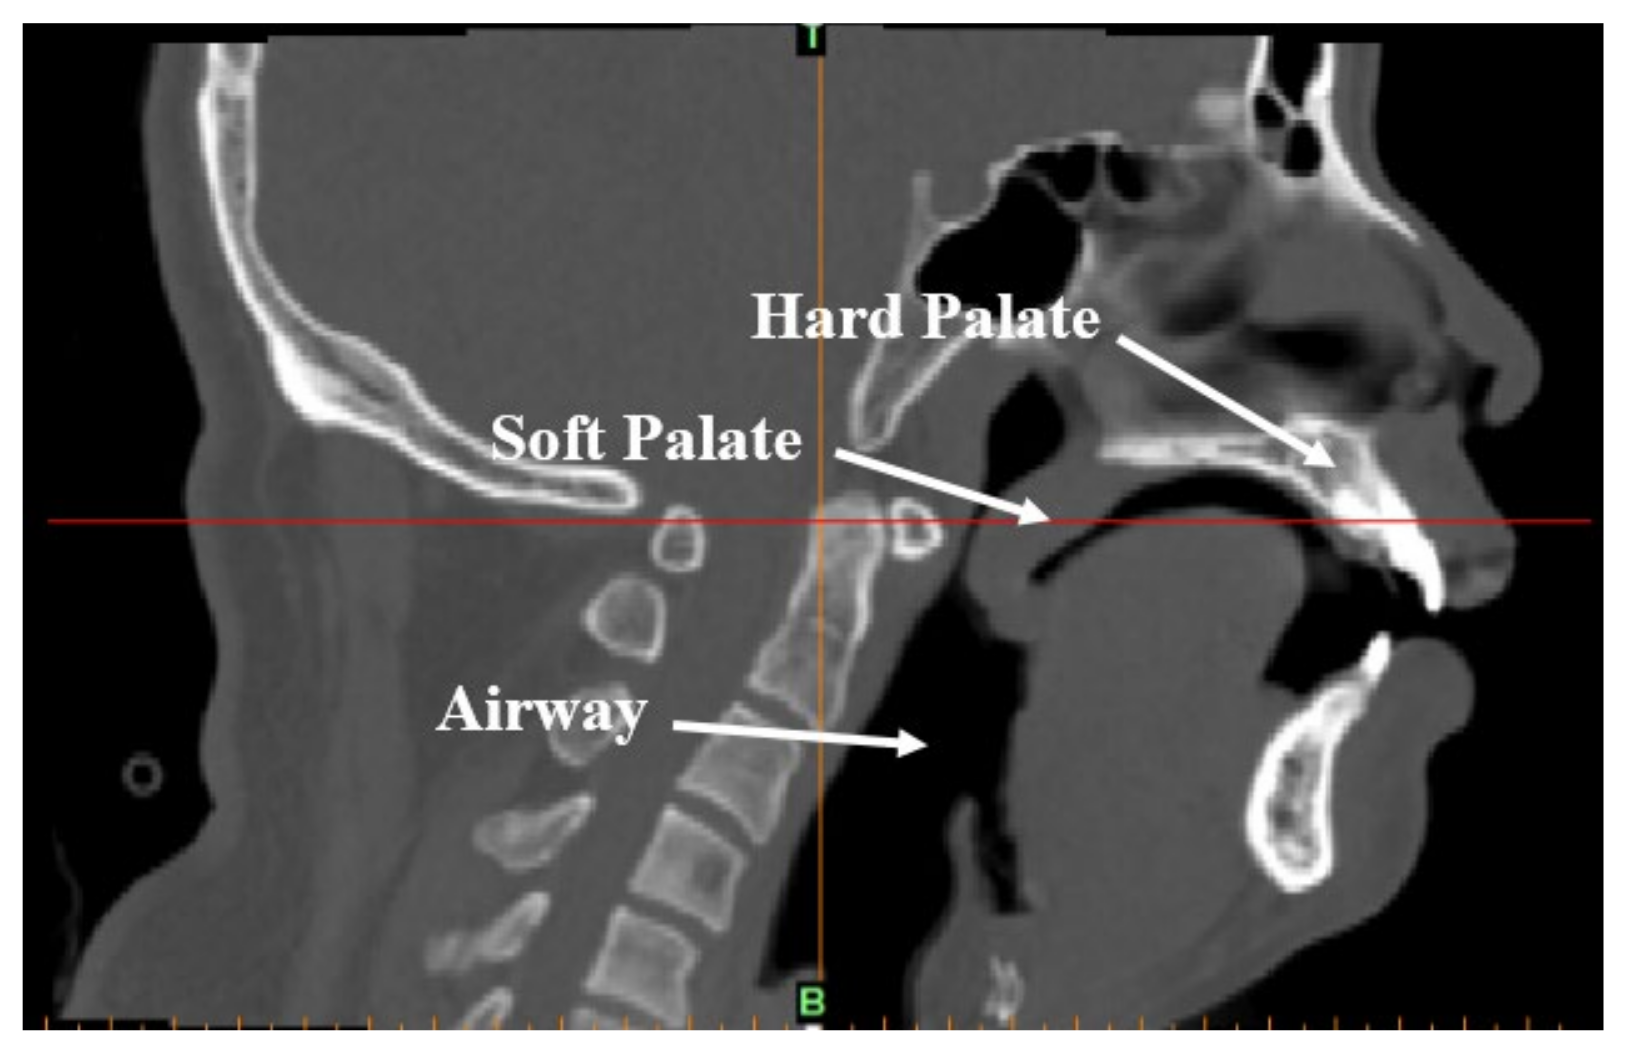

For minimizing the time in putting the patient to natural sleep for the scan, and eliminate the effect of tranquilizing drugs, the patient was required to stay awake for the entire night prior to the experiment and avoid consuming beverages or taking medication that was naturally exciting or tranquilizing before the examination. The patient was expected to sleep naturally in a supine position before the CT scan could commence. When the patient began to snore, the medical staff called the patient’s name gently and the patient did not wake up, confirming the patient was in a state of deep sleep. A Dy-volume scan from the basis cranii to the cricoid cartilage was performed on the patient using a Toshiba Aquilion ONE 640-slice dynamic organ volume CT scanner (Toshiba, Tokyo, Japan) to obtain the CT data of the patient’s upper airway during natural sleep, as shown in Figure 1. The scan time was set to 10 s and the scan thickness was 0.5 mm. When the scan was completed, DICOM format images were obtained and are shown in Figure 2.

Figure 2.

CT-scanned image of the upper airway of an OSAHS patient in a supine position and sleeping naturally.

After simplification of the data obtained from the nasal tissue, a quasi-3D FE model of the upper airway and its surrounding tissues was constructed and is shown in Figure 3. The thickness of the FE model was 10 mm. There were 88,693 nodes and 77,390 elements for the upper airway fluid field, 9240 nodes and 10,130 elements for the soft palate, and 8349 nodes and 6840 elements for the hard palate. Hexahedral elements were adopted in the solid and fluid domains of the upper airways, addressing with the incompressibility problem with a full integration formulation. In the model, the solid domain of the hard palate was set as the fixed boundary. The airway was modelled as fluid, and the junction between the airway and the soft palate was modelled by coupling the surfaces.